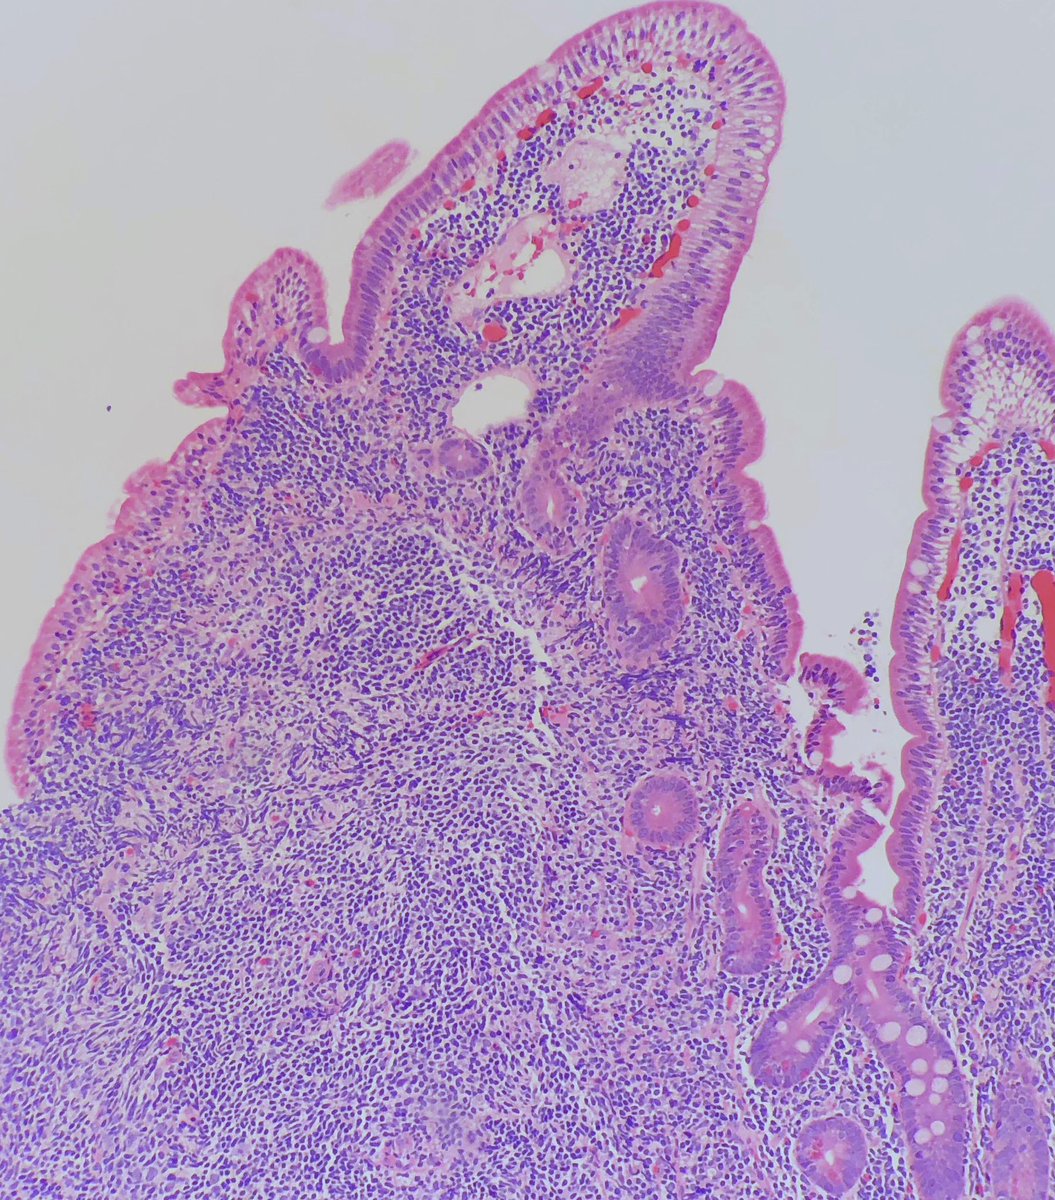

@StanfordPath Saturday!

45 YO woman with LBO. Colonoscopy shows cobblestoning. R/o Crohns

Mucosal ulceration with corkscrew glands in the lamina propria and submucosa. These glands are also on the serosa and in the muscularis propria

#stanfordpathsaturday#pathologytwitter pic.twitter.com/xlabjhtZOn